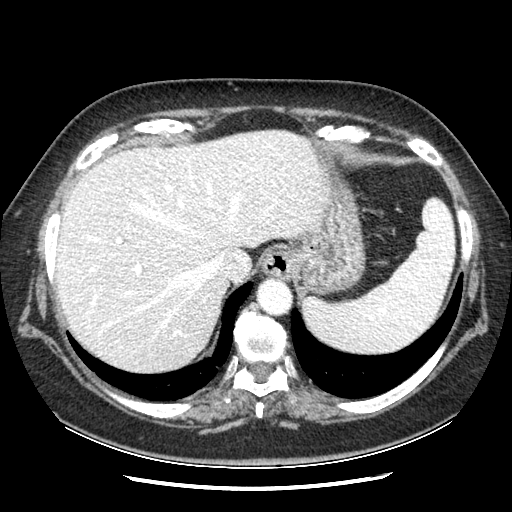

Generated VENOUS CT scan (A→B translation)

Full window (WL 1023.5, WW 4095 β†’ Low βˆ’1024, High +3071)

Lung window (WL -600, WW 1500 β†’ Low βˆ’1350, High +150)

Mediastinum window (WL 40, WW 400 β†’ Low βˆ’160, High +240)